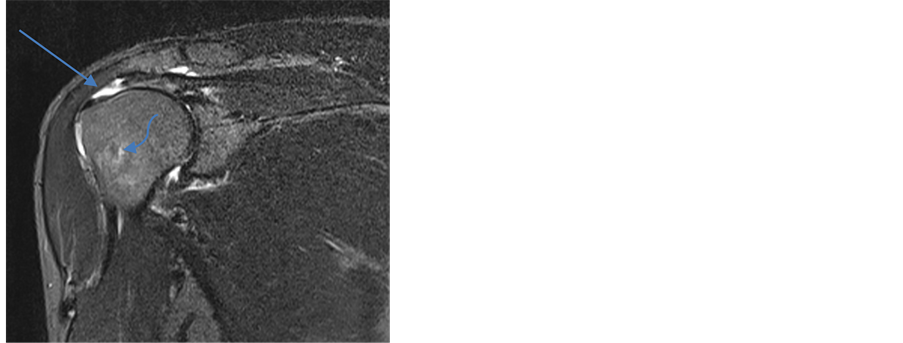

Recognized classification were used for the diagnosis of types of RCT and to categorize them for statistical calculation [4] [14] - [16] . Two MRI images have been shown to show partial thickness tear (PTT) and full thickness tear (FTT) in Figure 1 and Figure 2.

Figure 2. Coronal T2 weighted fat-suppression: MRI appearance of full thickness tear (arrow) at the insertion of supraspinatus tendon. Also humeral head edema (curved arrow) and shoulder joint effusion can be seen.

For the diagnosis of full-thickness rotator cuff tears by MRI (Figure 2), there was a high degree of sensitivity, specificity and accuracy (100%, 98.7% and 98.8%) respectively but these percentages are based on only seven cases. The size of full-thickness tears ranges from 0.7 cm to 4 cm in MRI. MRI showed only one false-positive rotator cuff tears which was proven surgically.